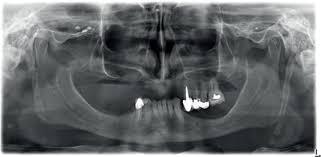

We provide Panoramic dental x-ray services which use a very small dose of ionizing radiation to capture the entire mouth in one image. It is commonly performed by dentists and oral surgeons in everyday practice and may be used to plan treatment for dentures, braces, extractions, and implants.